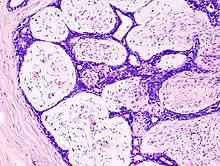

| Histopathologic image of breast fibroadenoma. Core needle biopsy. H&E stain. | |

Fibroadenoma of the breast is a benign tumor composed of a biplastic proliferation of both stromal and epithelial components.[14][15] This biplasia can be arranged in two growth patterns: pericanalicular (stromal proliferation around epithelial structures) and intracanalicular (stromal proliferation compressing the epithelial structures into slit-like spaces).

These tumors characteristically display hypovascular stroma compared to malignant neoplasms.[16][17][11] Furthermore, the epithelial proliferation appears in a single terminal ductal unit and describes duct-like spaces surrounded by a fibroblastic stroma. The basement membrane is intact.[18]

Fibroadenoma histology (H&E). The image demonstrates intracanalicular morphology (bottom left) and pericanalicular morphology (top right)

Histopathologic image of breast fibroadenoma. Core needle biopsy. Hematoxylin & eosin stain.

Histopathologic image of breast fibroadenoma showing proliferation of intralobular stroma compressing and distorting the epithelium. H&E stain.